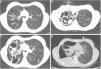

(A) Thoracic CT undertaken in 2010, where are identifiable cystic and cylindrical bronchiectasis more prominent in the right side. (B, C) Thoracic CT during hospitalization of the patient in 2011, showing pulmonary thick-walled cavities, with some material within the cavity, and also multiple new scattered nodular opacities, as well as some peripheral pleural based areas of consolidation. (D) Right sided hydropneumothorax.

The patient was a 20-year-old female with CF (F508del/F508del) diagnosed at age 3. She presented with lung and sinus involvement characterized by cystic, cylindrical and varicose bronchiectasis more prominent in right upper lobe (Fig. 1A), severe obstructive ventilatory defect (FEV1 41%), chronic colonization by methicillin-sensitive Staphylococcus aureus, AF and Candida spp. in repeated sputum cultures, as well as chronic sinusitis and nasal polyposis. The patient had a history of recurrent hospitalizations due to haemoptysis, some requiring embolization. She also had exocrine pancreatic insufficiency, poorly controlled diabetes, hepatic cirrhosis and presented undernourished (IMC 17.5kg/m2).

At the time of transfer to the adult clinic, there was evidence of increasing values of total immunoglobulin (Ig) E (between 387 and 790IU/mL) and elevated specific IgE (5.5IU/mL) and IgG (116 mgA/L) to AF, as well as the presence of precipitins to AF. Despite these values, the patient remained clinically stable, without lung function decline or worsening of arterial blood gas values or recent changes in chest X-ray. Taking this into account and due to the high risk of diabetes decompensation and hepatotoxicity, it was decided against corticosteroid or antifungal treatment. She was started on a pulmonary rehabilitation program in hospital and was referred for evaluation for lung and liver transplantation. After 1 year, the patient was admitted to the pulmonology ward, complaining of cough worsening, increase in sputum volume and purulence, dyspnea, bloody sputum and fever, which had evolved over 4 weeks. It was at this stage that occurred the first isolation of Pseudomonas aeruginosa from sputum culture, which led to IV tobramycin and ceftazidime. Pseudomonas aeruginosa, AF and Aspergillus flavus persisted to grow in sputum. Meanwhile, she underwent bronchial embolization due to haemoptysis. On day 7, the patient developed pleuritic chest pain, with evidence of worsening of pulmonary opacities in chest X-ray and a significant increase in total IgE (1378IU/mL) and specific IgE (9.15IU/mL) and IgG (>200 mgA/L) to AF. Treatment for ABPA exacerbation was started with oral prednisolone (1.5mg/kg) and itraconazole (5mg/kg). After initial improvement, she presented clinical worsening, recurrence of fever and development of new cavities and nodular opacities on CT (Fig. 1B and C). Therefore vancomycin was added, the antifungal was switched to IV voriconazole and prednisolone dose reduced, allowing for the diagnosis of sub-acute invasive aspergillosis. However, she continued to deteriorate and developed a right-sided hydropneumothorax (Fig. 1D) and died the following day.